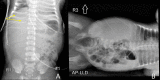

Figure 1. Anteroposterior (A) and left lateral decubitus (B) radiographic views of the abdomen.

The images demonstrate absence of gas in the right hemiabdomen and a few small coarse calcifications predominantly in the upper abdomen (yellow arrows; A). There is a mass effect causing deviation of the UVC catheter to the left as well as displacement of the bowel loops to the left. AP-LLD: anteroposterior left lateral decubitus